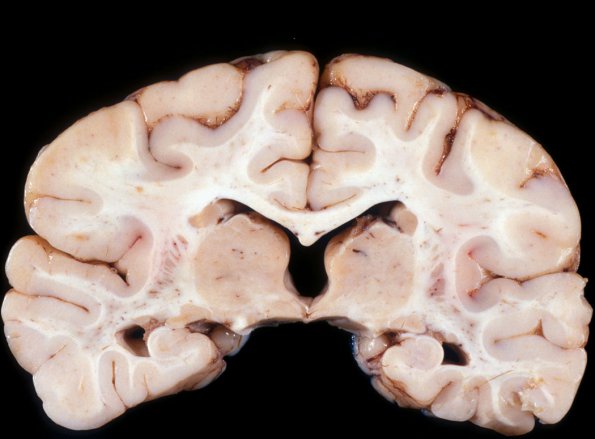

1A3 Microencephaly (Case 1) Gross 1

At the level of the thalamus, there is mild third ventricle and temporal horn expansion.